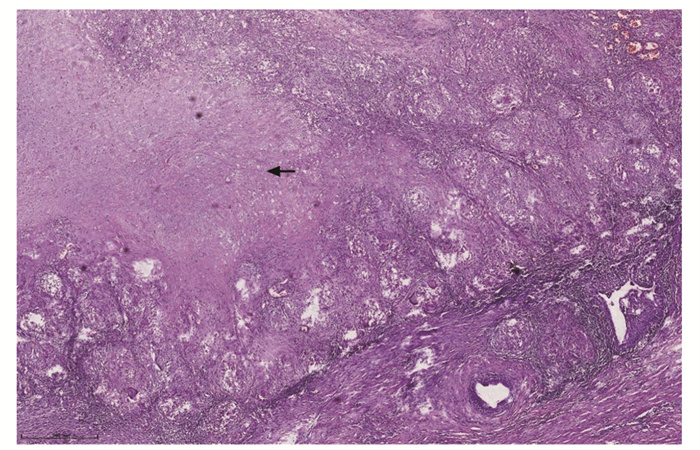

结果  共纳入睾丸和附件病变患者317例,平均年龄(38.72±19.74)岁,临床症状以阴囊区肿大、疼痛为主(88.01%, 279/317),肿瘤性疾病85例(26.81%,85/317)、非肿瘤性疾病232例(73.19%,232/317)。病变组织大体表现:肿瘤性疾病的病灶直径2~17 cm,呈结节或分叶状,切面为实性或囊实性,部分区域可见出血或坏死;非肿瘤性疾病的病灶直径0.6~8 cm,多呈囊性,囊壁较光滑,部分呈实性结节状。85例肿瘤性疾病患者中,平均年龄(38.09±14.52)岁,恶性肿瘤占比96.47%,肿瘤类型依次为生殖细胞肿瘤(88.24%,75/85)、淋巴造血系统肿瘤(4.71%,4/85)、间叶肿瘤(4.71%, 4/85)、间质细胞瘤(1.18%,1/85)、附睾乳头状囊腺瘤(1.18%,1/85),其中生殖细胞肿瘤中,主要为精原细胞瘤(66.67%,50/75),其次为混合性生殖细胞肿瘤(14.67%,11/75)、胚胎性癌(12.00%,9/75)。4例淋巴造血系统肿瘤均为弥漫性大B细胞淋巴瘤。232例非肿瘤性疾病患者中,平均年龄(38.94±21.36)岁,以鞘膜积液最为常见(56.03%,130/232),其次为炎症性疾病(31.03%,72/232)、睾丸发育异常(8.62%,20/232),睾丸扭转/梗死(3.88%,9/232)和睾丸附件囊肿(0.43%,1/232)较少见。睾丸与附睾结核(77.78%,56/72)是炎症性疾病的最主要类型。

Results  There were 317 cases of testicular and adnexal lesions diagnosed by pathology, with the mean age of (38.72±19.74) years and the clinical manifestations mainly characterized by swelling and pain in the scrotum area (88.01%, 279/317). There were 85 cases of neoplastic diseases (26.81%, 85/317), in which malignant tumors accounted for 96.47%, with an average age of (38.09±14.52) years. There were 232 cases of non-neoplastic diseases (73.19%, 232/317), with an average age of (38.94±21.36) years. The gross manifestations of the lesions were as follows: the lesions of the neoplastic disease were 2-17 cm in diameter and were nodular or lobulated, the sections were solid or cystic-solid, and bleeding or necrosis could be seen in some areas; the lesions of non-neoplastic diseases were 0.6-8 cm in diameter and were mostly cystic with smooth cystic wall, and some lesions were solid nodules. Among neoplastic diseases, the tumor types were germ cell tumors (88.24%, 75/85), lymphohematopoietic tumors (4.71%, 4/85), mesenchymal tumors (4.71%, 4/85), leyding cell tumor(1.18%, 1/85), and papillary cystadenoma of the epididymis (1.18%, 1/85). Among germ cell tumors, seminoma were mainly type (66.67%, 50/75), followed by mixed germ cell tumor (14.67%, 11/75), embryonal carcinoma (12.00%, 9/75). All 4 cases of lymphohematopoietic tumor were diffuse large B-cell lymphoma. Among non-neoplastic diseases, hydrocele accounted for 56.03% (130/232), followed by inflammatory diseases (31.03%, 72/232) and testicular dysplasia (8.62%, 20/232), testicular torsion/infarction (3.88%, 9/232) and testicular adnexal cyst (0.43%, 1/232) accounted for a lower proportion. Testicular and epididymal tuberculosis (77.78%, 56/72) was the main type of inflammatory diseases.